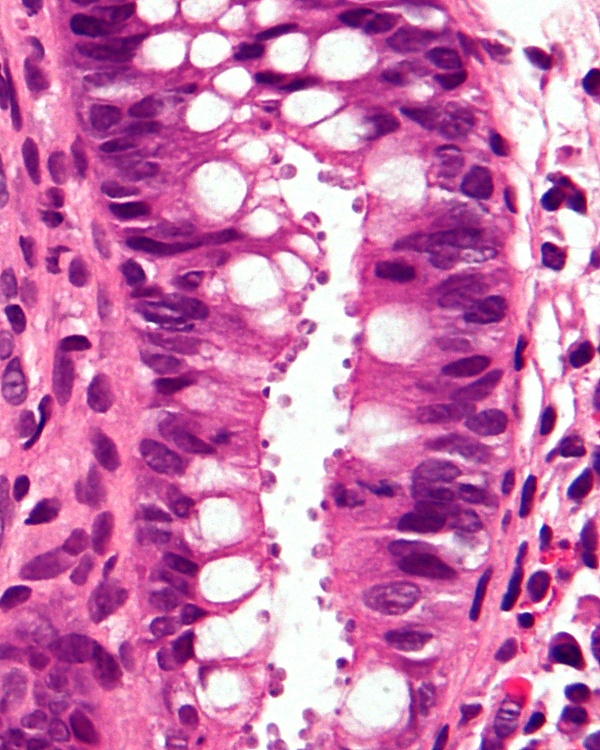

Существуют различные диагностические тесты для выявления криптоспоридиоза. Они включают в себя микроскопирование, окрашивание и обнаружение антител. Микроскопия используется для обнаружения ооцист в фекалиях пациента[9]. Для концентрации и выявления спороцист в пробе кала используются модифицированный метод центробежной плавучести сульфата цинка и метод плавучести сахара Шелтера[14]. Методы окраски включают кислотно-быстрое окрашивание, придающее ооцистам красный цвет. Также может быть использовано окрашивание красителем Гимза. Часть тонкой кишки может быть окрашена гематоксилином и эозином, что выявляет ооцисты, прикреплённые к эпителиальным клеткам[6]. Кроме того, применяется люминесцентная микроскопия проб, окрашенных аурамином[9].